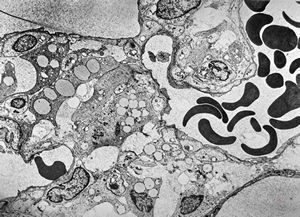

F,68y. | xanthomatous cell in atherosclerotic plaque - a. vertebralis